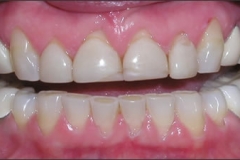

This young patient was self-conscious about the appearance of her short teeth and gummy smile. Through crown lengthening and tooth whitening procedures, we were able to create a beautiful, more mature smile.